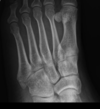

Bico talar

Coalizão calcaneonavicular.